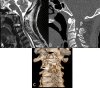

Concomitant Occurrence of the Ossified Posterior Longitudinal Ligament with a Posterior C2 Defect